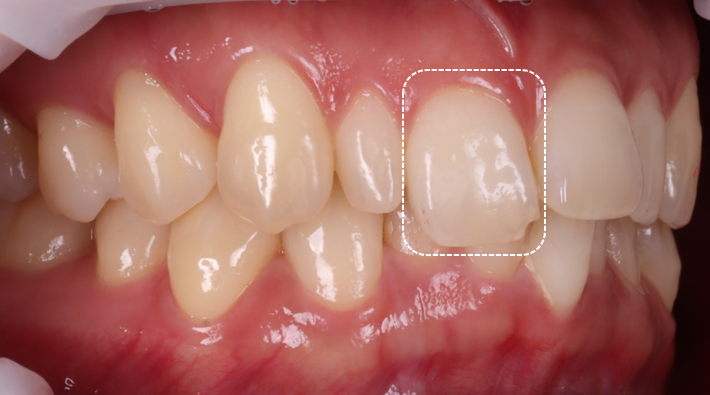

검진을 해보니 오른쪽 위 두 번째 앞니(측절치)는 전형적인 왜소치였고 반대편 두 번째 앞니는 크기와 형태가 정상이었어요.

왜소치는 반대쪽 측절치와 최대한 비슷한 크기와 형태를 기준으로 직접 왜소치 레진 비니어로 크기를 만들어주고,

깨진 앞니는 깨진 부분만 채우는 방식이 아니라 표면을 레진으로 비니어링 하듯 정리해서 전체 라인이 자연스럽게 이어지도록 계획했어요.

표면을 레진으로 정리하면서 앞니들이 한 줄로 가지런해 보이도록 평면을 맞춰주는 데 신경을 많이 썼어요.